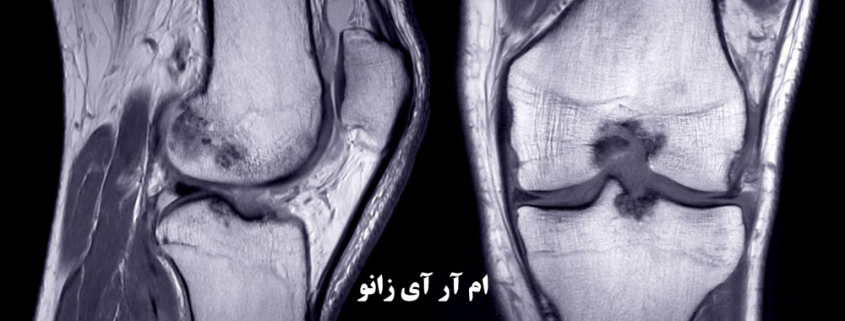

ام آر آی (MRI) زانو یک روش تصویربرداری غیرتهاجمی است که با استفاده از امواج رادیویی و میدان مغناطیسی قوی، تصاویر دقیق و پرجزئیاتی از ساختارهای داخلی زانو (استخوانها، غضروف، تاندونها، رباطها و عروق خونی) ایجاد میکند.

برخلاف عکسبرداری با اشعه ایکس که فقط استخوانها را به خوبی نشان میدهد، ام آر آی زانو در کرج، بهترین روش برای بررسی بافتهای نرم است.

تشخیص دقیق پارگی مینیسک، آسیبهای رباط صلیبی (ACL/PCL) و مشکلات غضروفی تنها با یک ام آر آی باکیفیت امکانپذیر است.